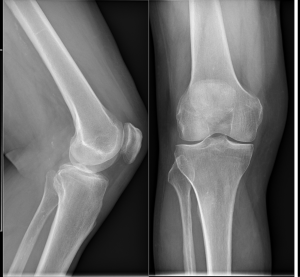

Princip vyšetření je založen na schopnosti rentgenového záření pronikat hmotou a dle vlastností jednotlivých tkání se specificky zeslabovat. Výsledkem je obraz zachycený na citlivý materiál – rentgenový film či detekční systém přístroje. Rentgenové vyšetření se hodí zejména k posouzení kostí a plic. Dále je možné např. z obsahu plynu ve střevech posoudit průchodnost střeva. Na snímcích lze hledat cizí kovová tělesa v těle.

Provádíme kompletní spektrum základních i speciálních skiagrafických vyšetření skeletu i měkkých částí lidského těla.

Ukázky RTG snímků